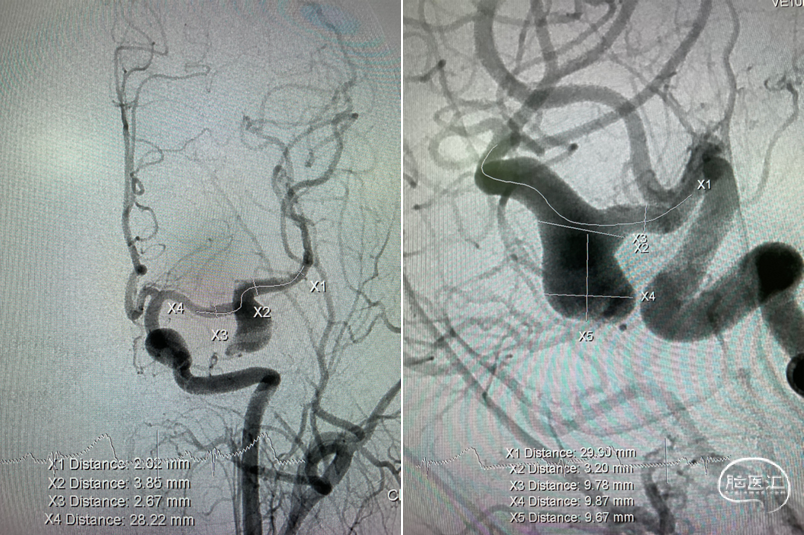

病变部位造影:

术前难点分析

手术方案

1. 颅内大动脉瘤瘤颈较宽,往往需要支架辅助弹簧圈栓塞才能达到一定治疗效果,且复发率较高。

2. 近年来血管内治疗颅内动脉瘤的技术发展迅速,尤其是以Pipeline为首的血流导向密网支架的问世,使得颅内动脉瘤的治疗迈上了新台阶,将治疗理念从囊内栓塞转向了载瘤动脉重建。

拟行:密网支架血管重建+弹簧圈栓塞术。